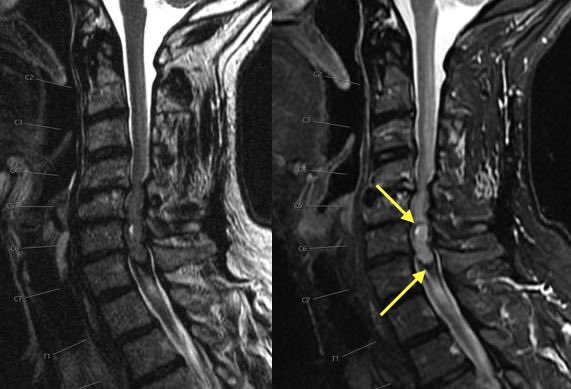

What is the most likely diagnosis in this 65 y/o M presenting w/ leg weakness, hyperreflexia, spasticity and absent vibration sense in the LE? #neu